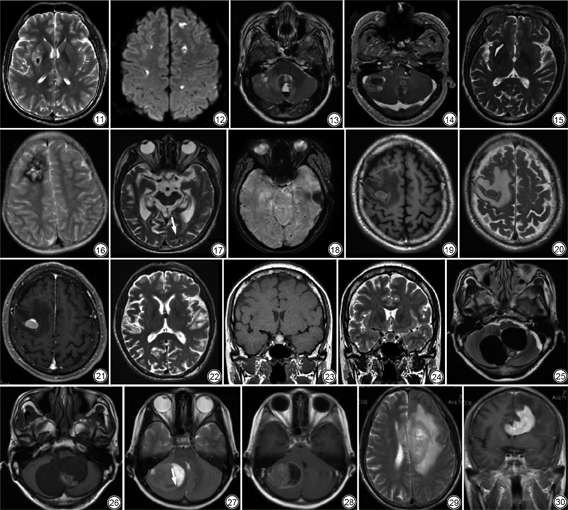

血液溢出血管外后,随着氧的消耗,血红蛋白转变为脱氧血红蛋白,为急性期,T1WI和T2WI均为低信号,以T2WI为明显。随着氧的进一步消耗,脱氧血红蛋白转变为高铁血红蛋白,进入亚急性早期,此时红细胞膜仍完整,高铁血红蛋白位于红细胞内,在T1WI上呈高信号,T2WI上呈明显低信号[2]。

颅内出血根据部位分为脑内血肿、蛛网膜下腔出血、硬膜下血肿和硬膜外血肿。引起脑内血肿的病因有很多,包括高血压、血管畸形、凝血功能障碍、外伤、脑淀粉样血管病等,结合临床有助于病因的确定。血肿周围脑组织水肿,血肿可破入脑室,导致脑室铸形或出现血液平(图1, 2, 3, 4)。

蛛网膜下腔出血的病因包括外伤、动脉瘤破裂、动静脉畸形等(图5)。血液位于脑沟裂、脑池内和(或)脑表面,血液聚积最明显的部位多为出血处。

硬膜外血肿和硬膜下血肿多有外伤史。前者指血液积聚于硬脑膜与颅骨之间,轴位图像上呈凸透镜形,不跨越颅缝(图6)。后者指血液积聚于硬脑膜与蛛网膜之间,轴位图像上呈新月形,可跨越颅缝[3],不延伸至脑沟裂内;血肿机化后牵拉血管致其破裂再出血,则可形成液平(图7);大脑镰和小脑幕旁的血肿为硬膜下血肿。

出血性梗死指缺血性卒中后,梗死区域或梗死血管分布区出现出血灶。发病原因目前认为与卒中后血脑屏障破坏和再灌注损伤有关[4]。其影像学表现分为三型:Ⅰ型,梗死区域内可见散在小点状出血,无占位效应;Ⅱ型,多个融合的点状出血,无占位效应;Ⅲ型,血肿位于梗死组织内,体积≤30%梗死灶,并有轻微占位效应。T2WI上表现为高信号病灶内点状、斑片状低信号(图8)。

静脉性脑梗死是由于脑内静脉回流受阻引起引流区脑组织水肿、脑梗死和脑出血。临床表现主要为“雷击样”头痛、癫痫及颅内压增高症状[5]。MRI上多表现为皮层、皮层下多发或孤立性病灶,不符合动脉分布区域或大于一支动脉分布区域,可累及双侧基底节区及丘脑。静脉性出血性脑梗死T2WI上表现为高信号梗死灶内见斑片状低信号[6](图9)。发现静脉窦内血栓有助于诊断,在增强T1WI和磁共振静脉造影(magnetic resonance venography,MRV)上呈充盈缺损。

外伤可引起脑组织、软脑膜和血管撕裂,造成多发灶状出血。病灶多位于着力点及其附近,或其对冲部位[7]。早期多表现为大片状T1低信号、T2高信号水肿,其内伴有出血,信号取决于出血时期(图10)。而病变晚期由于病变区脑组织坏死、液化,瘢痕修复,软化灶形成,表现为T1低信号、T2高信号,FLAIR低信号周围可见高信号胶质增生,并伴相邻部位脑萎缩。

慢性期血肿为出血2周后的血肿,高铁血红蛋白转变为含铁血黄素,沉积于血肿的边缘,在各序列上均为低信号。大的血肿慢性期T2WI上表现为围绕高信号中心的环形低信号,可见负占位效应(图15);小的血肿可仅为条状低信号,扩散加权成像(diffusion weighted imaging,DWI)显示更清楚。

海绵状血管畸形由脑内簇状分布的异常血管组成,含铁血黄素沉积和胶质细胞变性沉积于透明变的毛细血管周围,管腔内充满血液,并伴有不同程度血栓形成。患者多无症状,或有头痛、癫痫等。多数位于幕上,幕下者常位于脑干,病变可单发或多发。MRI信号特点分为四型:Ⅰ型,亚急性出血,T1WI及T2WI均为高信号;Ⅱ型,信号混杂,典型者呈“爆米花状”;Ⅲ型,慢性出血,各序列低信号,常见于家族型海绵状血管畸形;Ⅳ型,点状微出血,仅T2*WI与SWI显示清楚。病灶一般无占位效应和灶周水肿,血管造影检查多阴性[11](图16)。

脑淀粉样血管病是由β-淀粉样蛋白在皮层动脉和软脑膜动脉壁异常沉积所引起。是老年人非外伤性及非高血压性脑出血的常见原因,随年龄增高,发病率增加,临床表现主要是脑出血、脑梗死及认知功能障碍[12]。病灶多位于皮层和皮层下,小脑、基底节区少见,MRI上可见弥漫多发微出血灶和血肿,血肿形态不规则,且病变因可反复出血,因而信号混杂[13]。SWI有助于本病的诊断(图17,18)。脑微出血(cerebral microbleeds,CMBs)目前在临床得到较多关注,CMBs主要表现为血管周围T2WI及SWI低信号。CMBs见于如阿尔兹海默病、脑淀粉样血管病、卒中等多种疾病中,对于卒中患者存在CMBs则提示可能预后较差[14]。